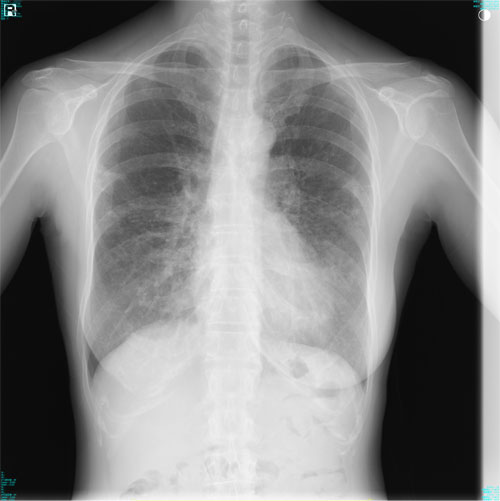

肺X線画像

- 2023.07.27 肺炎と診断された画像(国立系病院)